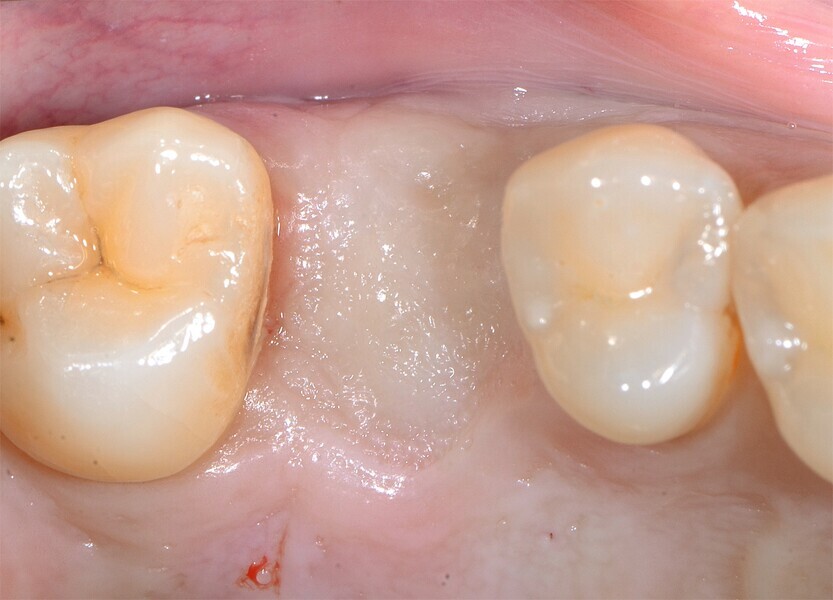

Fig. 3 : Cicatrisation de l’alvéole préservée.

Fig. 4 : Cicatrisation de l’alvéole préservée.

Fig. 5 : Cicatrisation de l’alvéole préservée.

La première phase du traitement implantaire a consisté à extraire la dent et à préserver l’alvéole au moyen d’une allogreffe et d’une membrane de collagène. Six mois après, l’os régénéré a permis de procéder à la seconde phase du traitement comportant la pose d’un implant deux pièces en céramique (Figs. 1–11).